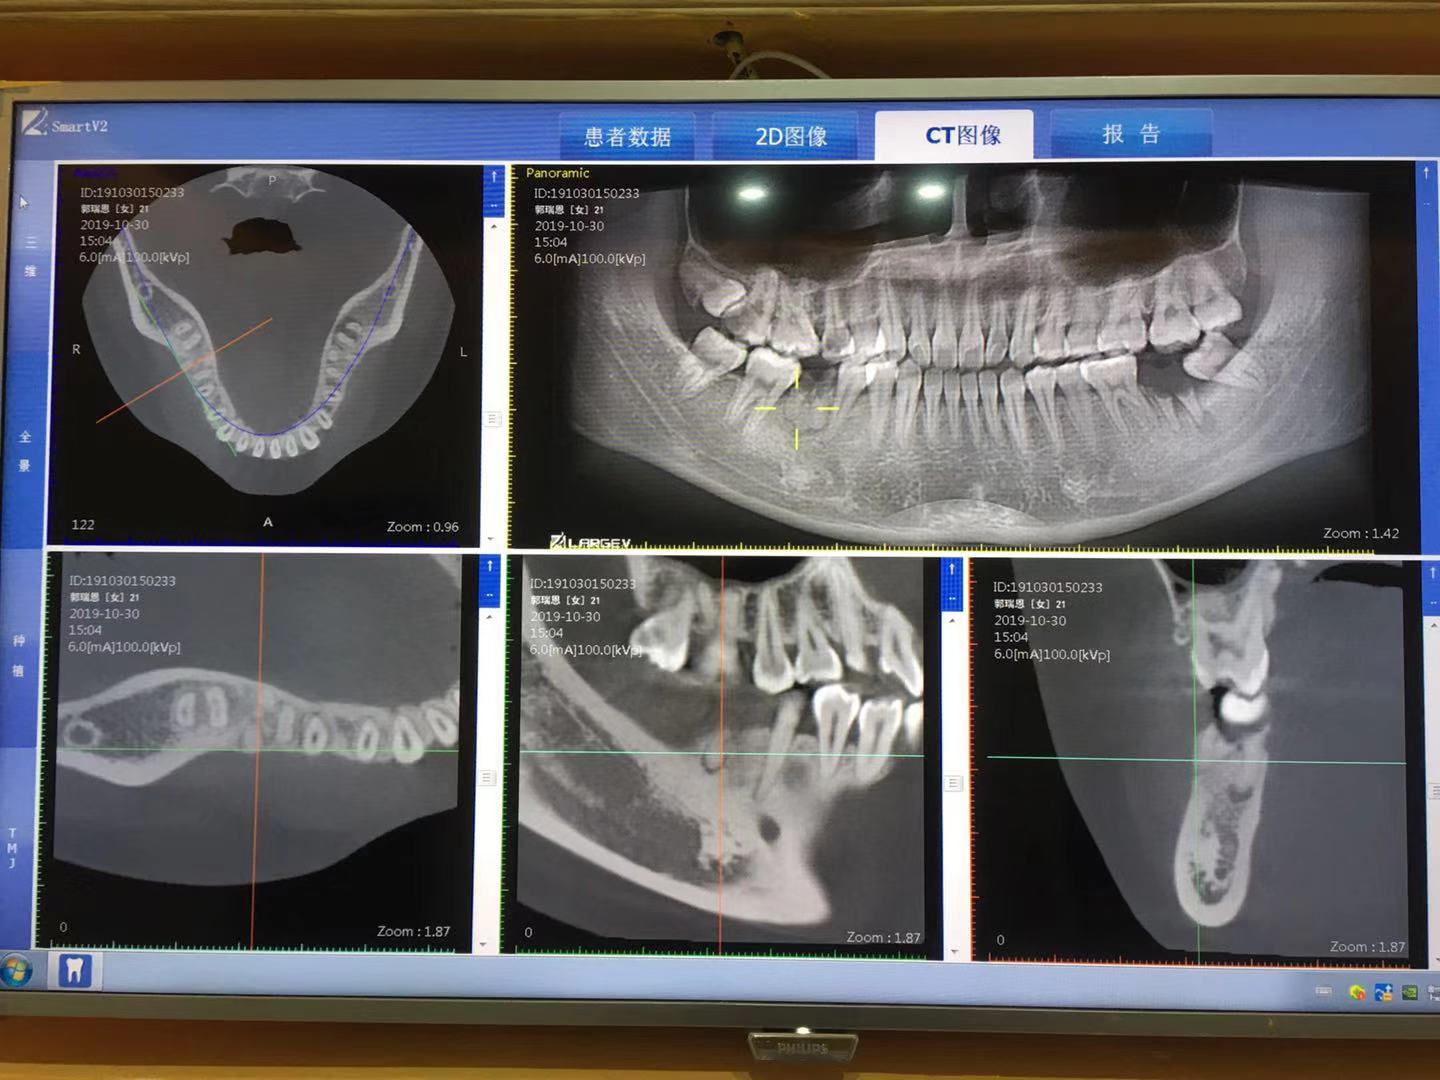

主页>種牙案例>种植案例